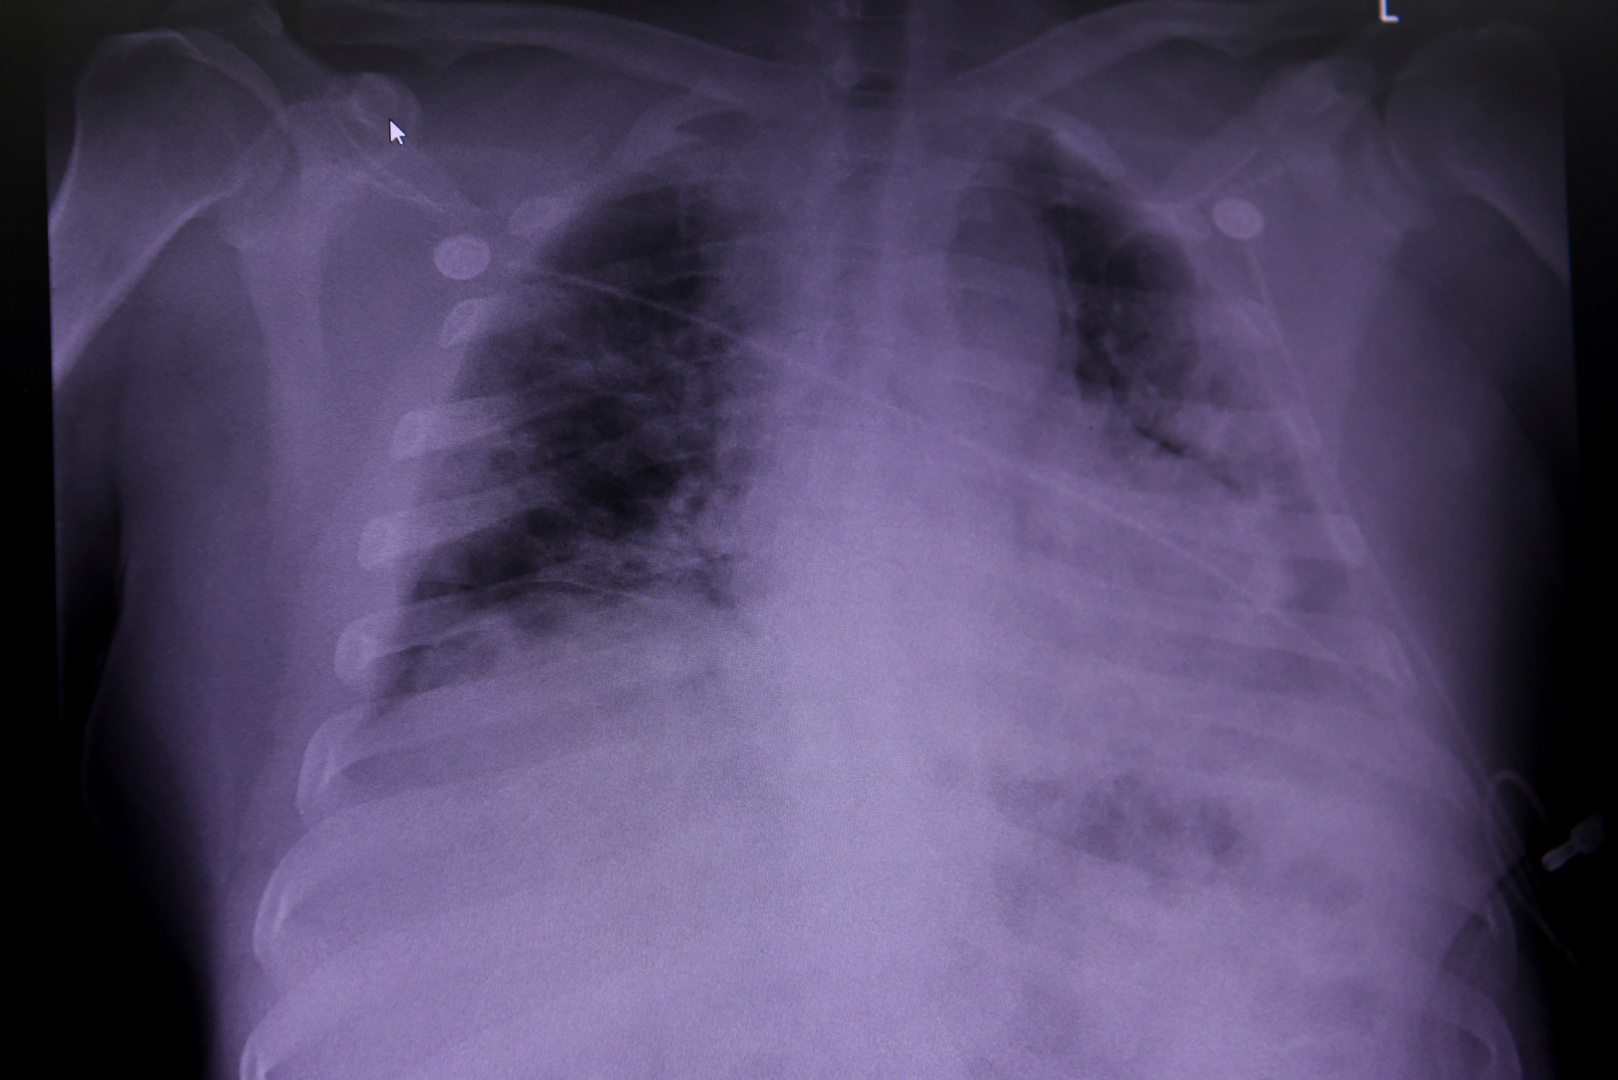

كورونا وسرطان الرئة.. التشابه والاختلاف

وقال رينتولا إنه رغم التشابه في الأعراض لدى المصابين بفيروس كورورنا والمصابين بسرطان الرئة، إلا أن هناك عدة اختلافات تساعد في التمييز بين الحالتين.

وأوضح الطبيب أن السعال الجاف المصحوب بضيق في التنفس والحمى وآلام في العضلات وفقدان حاسة الشم والتذوق قد تكون أعراضا لمرض كوفيد -19 (كورونا)، أما إذا كان السعال مرفوقا بدم لمدة أسبوعين أو ثلاثة أسابيع، وفي نفس الوقت نقص فقدان الوزن وآلام بالقفص الصدري فإن هذه الأعراض قد تشير إلى الإصابة بسرطان الرئة.